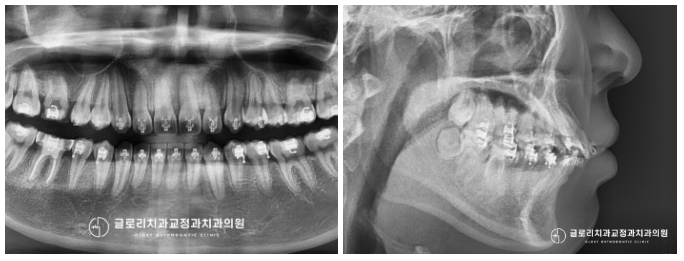

장치를 부착하여 이동을 돕고 있는 모습입니다.

다른 부가 장치의 도움 없이 브라켓과 와이어만으로만

현재 나타난 문제들을 개선 중에 있는데요.

이분의 경우 현재 돌출도가 괜찮다는 말씀을 하셨기에

삐뚤어진 곳만 고르게 바꿔드렸는데요.

『그래서 그런지 예상 기간보다

훨씬 단축되어 1년 만에 마칠 수 있었습니다.』

이전과는 달리 고르게 펴진 치열이 보이시나요?

훨씬 건강하고 안정적인 모습인데요.

이를 고르게 펴주어서 그런지

돌출은 치료를 하지 않았는데 불구하고

훨씬 안정적인 모습을 갖게 되었습니다^^